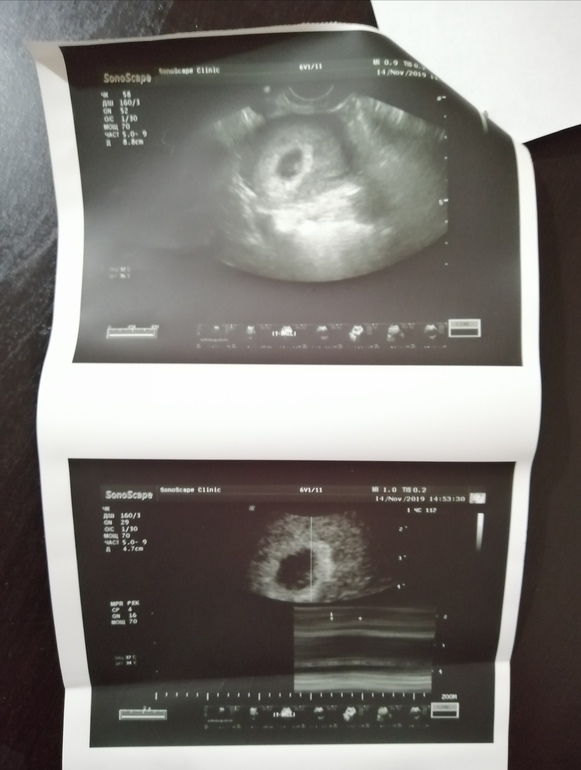

УЗИ, КТГ, доплерСегодня решилась сходить на первое УЗИ прям в свой день рождения. Очень переживала, боялась услышать что-то нехорошее. УЗИ делали трансвагинально, срок 6+2.

ПЯ - 16 мм

СБ - 112 уд/мин

КТР - 5 мм

Желточный мешочек - 3 мм

Жёлтое тело в ЛЯ - 20 мм